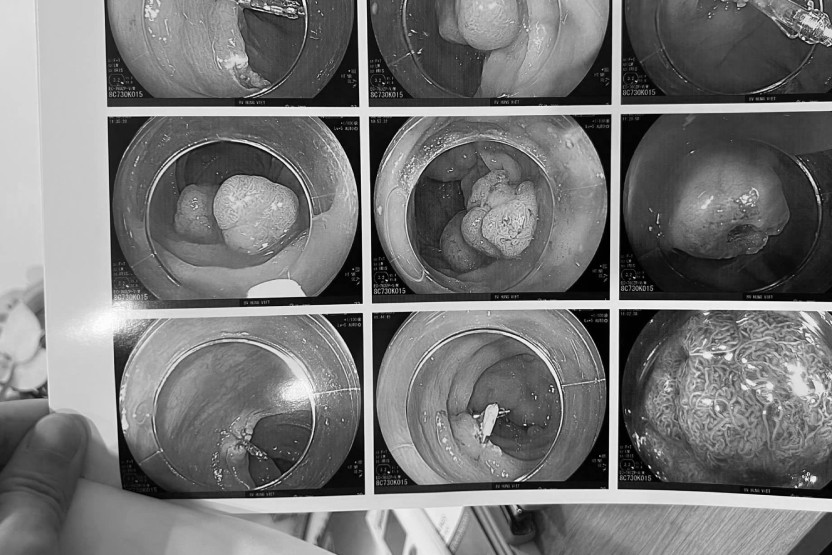

Bác sĩ Thành cảnh báo, 80% bệnh ung thư đại trực tràng phát triển từ polyp. Polyp ban đầu chỉ là các khối u do tăng sinh quá mức trong lòng đại tràng, hầu hết vô hại, lành tính. Một số trường hợp to lên gây tắc ruột và có thể phát triển thành ung thư đại tràng. Nếu không được phát hiện sớm, bệnh nhân có thể tử vong.

Người bệnh cần tầm soát thường xuyên, nội soi đại tràng khi 40 tuổi. Đây là cách tốt nhất phát hiện sớm bất thường ở lòng đại trực tràng.